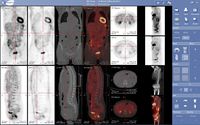

التصوير المقطعي بالإصدار البوزيتروني إنگليزية: Positron Emission Tomography أو PET تقنية تصوير في الطب النووي تسفر عن معطيات وصور ثلاثية الأبعاد لمجرى مختلف العمليات الوظيفية في الجسم. ويعمل الجهاز المصوّر على أساس اكتشاف أزواج من أشعة غاما المنبثفة بشكل غير مباشر عن نظير مشع مصدر للبوزيترونات (قائفة مشعة)، والتي يتم إدخالها إلى الجسم بعد أن ترتبط بجزيء فعال حيويًا). من ثم، يتم استبناء الصورة ثلاثية الأبعاد من الإسقاطات بشكل محوسب. في الآونة الأخيرة، أصبحت تستعمل أجهزة تسهل الاستبناء بواسطة استعمال التصوير الطبقي المحوسب بواسطة الأشعة السينية (أشعة إكس) والذي يتم إجراءه في نفس جهاز التصوير بالإصدار البوزيتروني وفي نفس الوقت.

إذا كان الجزيء الفعال حيويًا الذي يرتبط بالقائفة هو جزيء الـFDG (إحدى مضاهئات الجلوكوز)، فإنّ تصوير تركيز القائفة يعطي قياسًا للفعالية الأيضية في الجسم من منظار قدرة النسيج المحليّة على قبط الجلوكوز. مع أنّ استمعال هذه القائفة بات شائعًا في التصوير المقطعي بالإصدار البوزيتروني، فهنالك العديد من القائفات الأخرى التي قد تعطينا معلومات عن تراكيز جزيئات مختلفة في الجسم.

لإجراء التصوير، يتم حقن الشخص الخاضع للتصوير بقائفة التي هي عبارة عن نظير مشع ذي عمر قصير، وعادة ما تحقن المادة إلى الدورة الدموية. وعادة ما تحقن القائفة بعد أن يتم دمجها في جزيئات فعالة حيويًا. بعد فترة انتظار، يرتفع خلالها تركيز القائفة في الأنسجة المرغوب تصويرها، يتم وضع الشخص في جهاز التصوير التفرسي (الماسح). ويعرف الجزيء الأكثر استعمالاً في تصوير الإصدار البوزيتروني باسم فلوريد الجلوكوز منقوص الأكسجين (FDG)، وهو من السكريات، ويكون زمن الانتظار بعد الحقن لدى استعماله ساعة واحدة تقريبًا. في خلال عملية التصوير يتم تسجيل تركيز القائفة في النسيج، في حين تتحلل القائفة بشكل طبيعي وفق عمر النصف خاصتها.

وفق الإحصائيات الملتقطة من تزامن اصطدام أزواج فوتونات بالمفراس، بالإمكان حل هيئة معادلات لكمية فعالية القائفة المشعة في كل قطعة من النسيج المنشود على طول عدّة خطوط LOR. بهذا الشكل يتم تخطيط النشاط الإشعاعي لكل فوكسل في النسيج. الصورة النهائية تظهر جميع الأنسجة التي تركزت فيها القائفة المشعة، وهي صورة يستطيع أخصائي أشعة أن يقرأها ويستخلص منها الاستنتاجات.